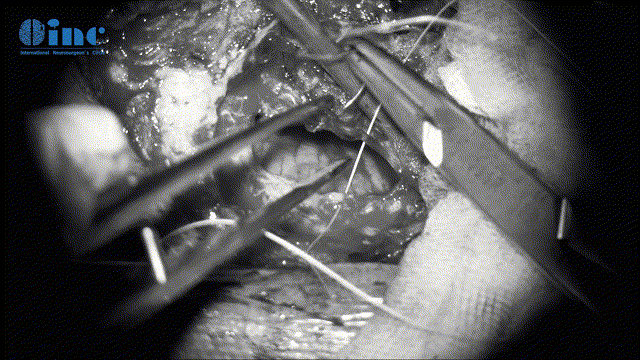

▼分离肿瘤基底和周边滑车神经保护(此次如伤及神经,可造成复视、斜视)

▼保神经下全切肿瘤(根据肿瘤质地、神经黏连程度及神经功能重要性,平衡保神经及肿瘤切除程度)

▼动眼神经表面肿瘤剥离、保护神经表面微小血管(如伤及动眼神经,可导致复视、眼睛闭合不紧、眼皮下垂)